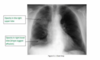

What is being shown on the image?

first pic: T1a N0 M0 - parietal pleura only, no nodes or invasion stage 2: T2 N0 M0 - pleura plus lung or diaphragm muscle invasion, still on one side and no nodes stage 3: T3, any N1 or N2 - deeper local invasion and or regional lymph nodes stage 4: T4, any N3 or M1 - spread to other side of the chest/pleura, or distant spread